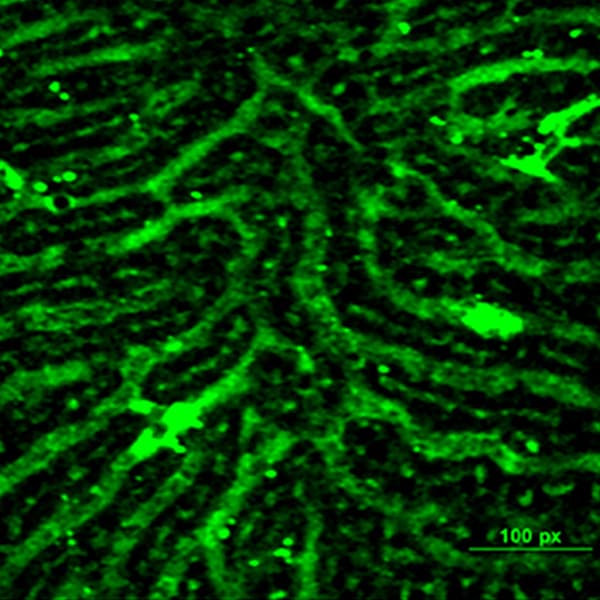

Liver sinusoidal blood vessels as seen using multiphoton microscopy.